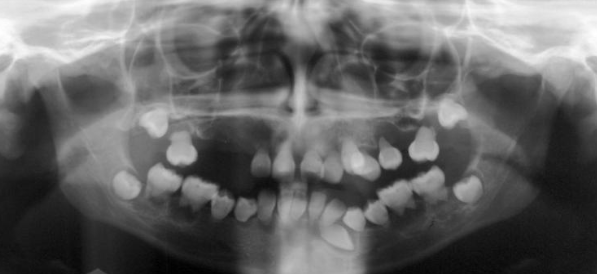

syndrome characterized by dental and clavicle abnormalities, AD inheritance, prolonged retention of deciduous teeth, numerous unerupted permanent and supernumerary teeth

cleidocranial dysplasia

found in gardner syndrome (20%) and cleidocranial dysplasia (more common)

hyperdontia (supernumerary teeth)